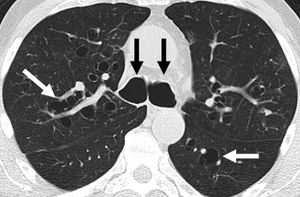

대부분의 기관지확장증 환자에게서 흉부 엑스레이는 비정상 소견을 보인다. 컴퓨터단층촬영(CT)은 진단을 확인하기 위해 권장되며, 질병의 분포를 설명하고 중증도를 등급화하는 데에도 사용된다. 방사선학적 소견에는 기도 확장, 기관지 벽 비후, 무기폐 등이 있다.[103] CT 스캔에서 볼 수 있는 기관지확장증에는 원주형, 정맥류형, 낭포성 기관지확장증의 세 가지 유형이 있다.[64]

CT 스캔으로 기관지확장증을 진단하는 소견. 흰색과 검은색 화살표는 질병의 특징인 확장된 기관지를 가리킨다.